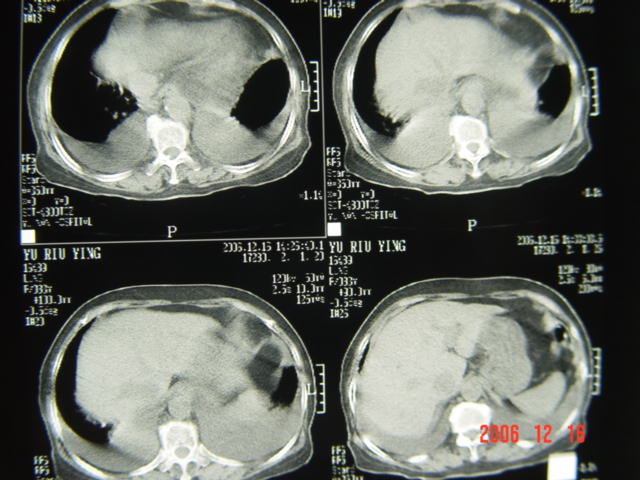

标题: CT5663:女、83岁,轻微咳嗽、左下胸痛。 [打印本页]

标题: CT5663:女、83岁,轻微咳嗽、左下胸痛。

左第八肋腋侧呈膨胀性骨质破坏,内侧见软组织密度肿块。左肺舌段呈楔形实变,基底近胸壁,尖端向肺门。双侧胸壁后缘见新月形水样密度区。

考虑:1、左第8肋骨转移瘤;

2、左肺舌叶肺栓塞可能性大;

3、双侧中量胸腔积液。